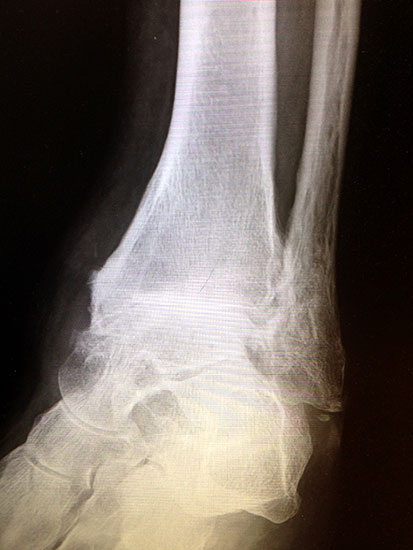

Erreichen eines schmerzfreien oberen Sprunggelenkes mit belastbarem und plantigrad aufsetzbarem Fuss (Abb. 1a und b) unter Verzicht auf die Bewegungsfunktion des oberen Sprunggelenkes. Operative Resektion der arthrotisch veränderten Gelenkflächen bis in den subchondralen frischen Knochen von Tibia und Talus. Fusion mittels Kompressionsschrauben oder Arthrodeseplatten, bedarfsweise Arthrodesenagel.

Abbildung 1a